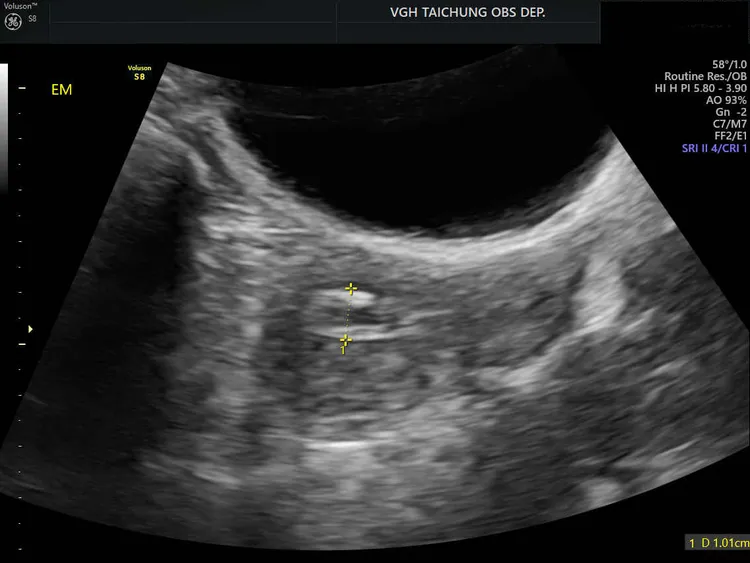

透過超音波可見患者子宮內有異常息肉。中榮提供